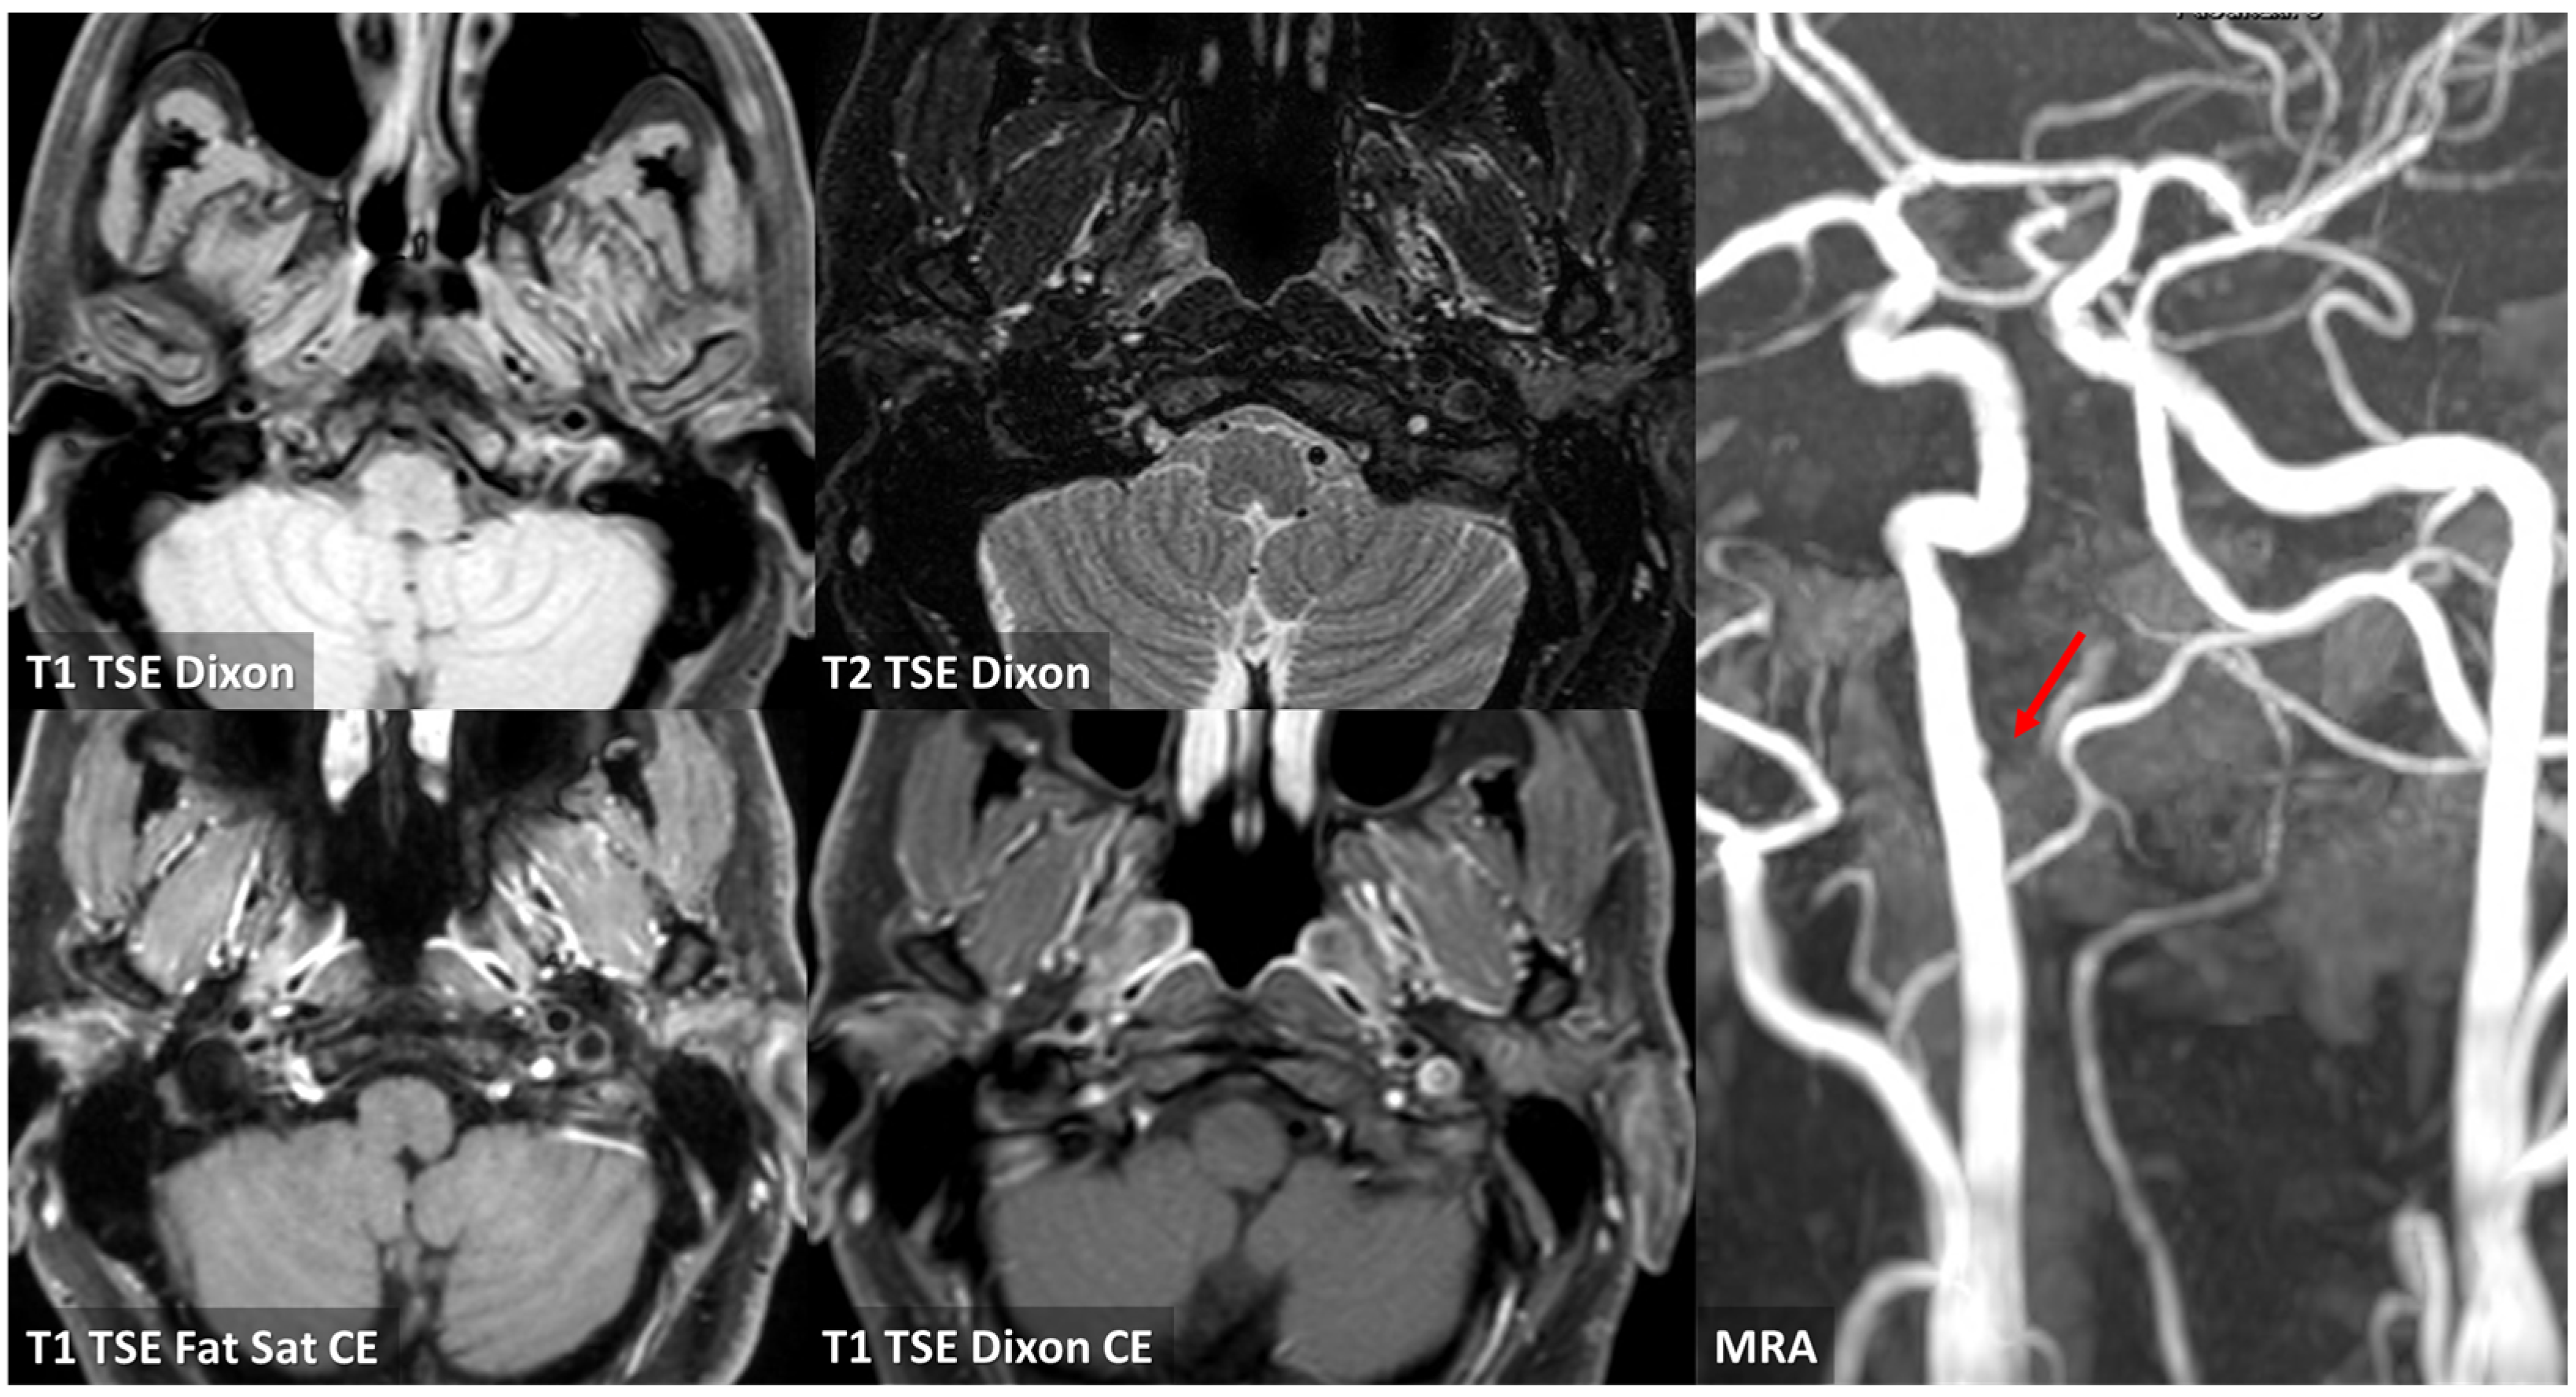

3.2. Case 2